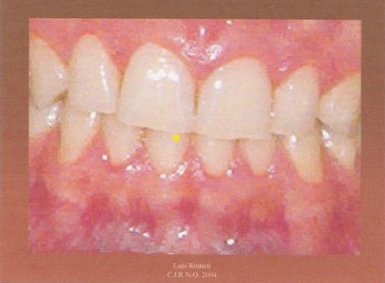

1.- Es conveniente adiestrar al paciente para que aprenda a realizar lateralidades izquierda y derecha desde su máxima intercuspidación. También es aconsejable poner un separador labial. Tras secar los incisivos superiores e inferiores con un rollo de algodón, marcamos un punto en la arcada inferior con el rotulador.